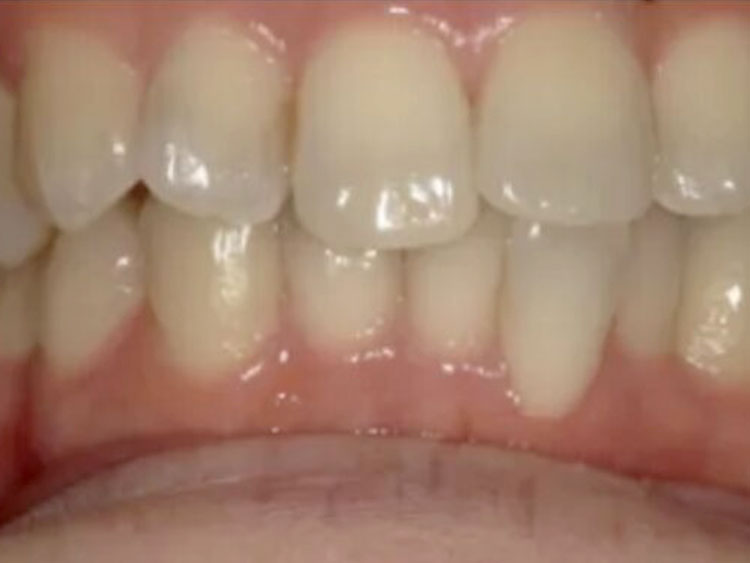

CASE 09

BEFORE

▶

AFTER

20代。 「前歯の傾きが気になる」「下の歯のガタつき」を主訴に来院。 検査の結果、上の前歯が下の前歯を深く覆ってしまう「過蓋咬合(Deep Bite)」の状態であり、見た目だけでなく噛み合わせの機能改善も必要でした。